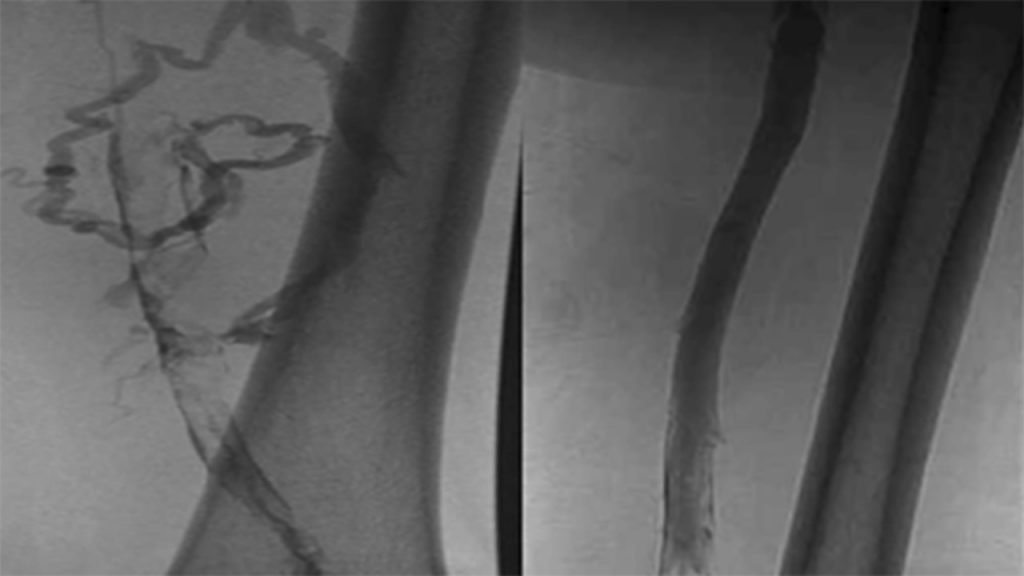

Duplex Ultrasound

A tool that uses sound waves to look at the flow of blood in the veins.